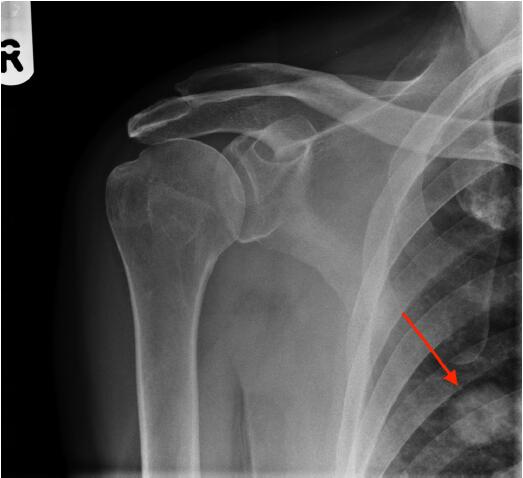

圖2肩X光片顯示一空洞性肺結(jié)節(jié),約2cm。很可能是原發(fā)性肺癌,需要轉(zhuǎn)診至肺癌多學(xué)科小組。

圖2右肩前位X光平片,紅色箭頭指示一空洞性肺結(jié)節(jié)